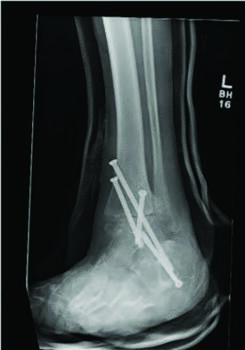

There are several studied and suggested surgical fixation options for treating complicated diabetic ankle fractures. As mentioned earlier, inappropriate treatment of these injuries can often lead to complications including the worst case scenario of Charcot arthropathy, and potential resultant limb loss. Hence, the common fundamental goals currently used for Charcot reconstruction also apply in ankle fracture fixation for patients with complicated diabetes.7 Specifically, these include obtaining a fixation construct with maximum rigidity and absolute stability, extending the fixation beyond the immediate zone of injury and planning incisions to minimize soft tissue trauma and optimize healing.4 Some fixation constructs suggested in recent literature include: circular external frame fixation; internal fixation using screws and plates; tibiotalocalcaneal (TTC) nail construct; and even locked fibular intramedullary nail fixation.4,8-10

Facaros and colleagues presented a case report of a patient with diabetes and neuropathy who sustained a displaced fibular fracture with significant joint subluxation and syndesmotic injury.11 Subsequent surgical intervention consisted of ORIF with plate fixation, multiple pro-syndesmotic screws and application of a multiplanar circular external fixator. This allowed a maximally stable and rigid construct and also allowed the patient to fully weight bear postoperatively on the external fixator. The patient underwent removal of the external fixator after 12 weeks without any long-term sequelae.11The use of multiple syndesmotic screws regardless of a syndesmotic injury is repeatedly suggested in the literature, as it allows for a more mechanically stable construct.4